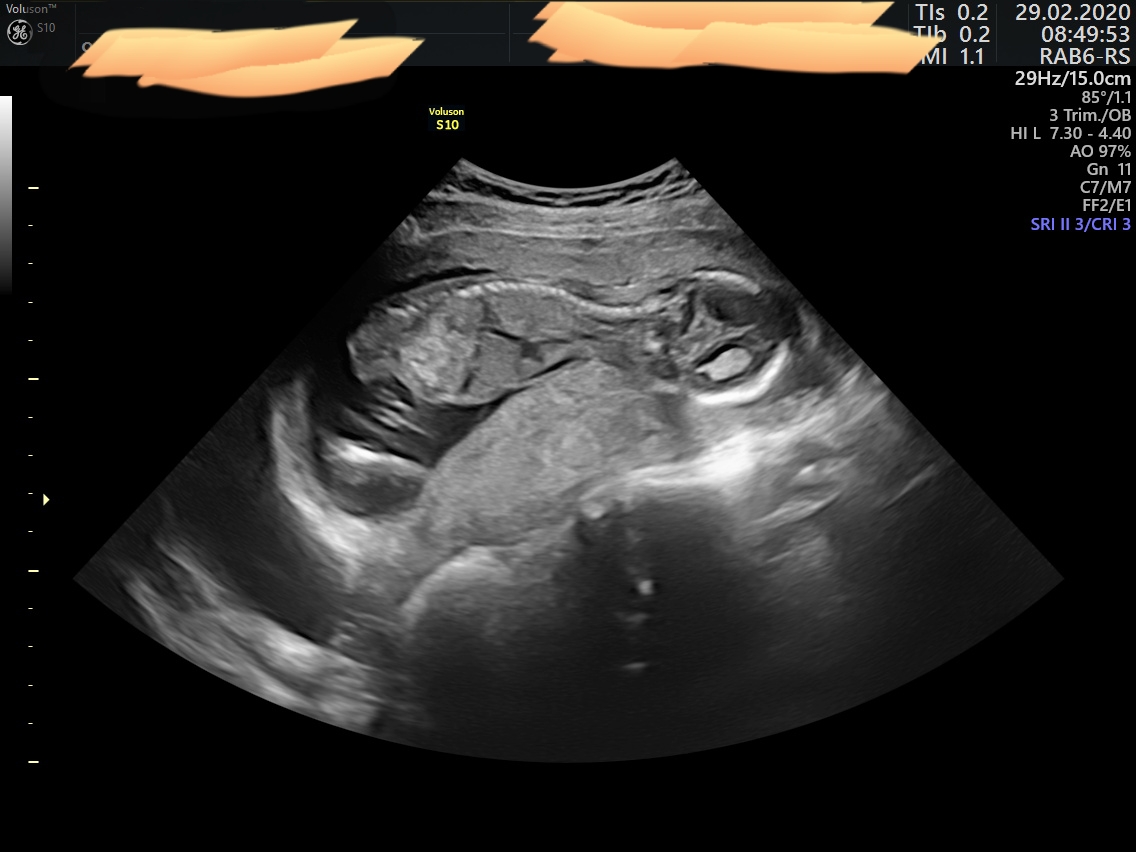

My byli na obou velkych utz i 3D v Brne v Prenatalu a pokazde holcicka... kdyz nam to na druhem utz potvrdil dr. Vlasin, tak uz jsem to brala jako jiste 😀 ale dr. ve 14tt rekl jasne, ze to jiste neni, jen ze ON VIDI holku... to je normalni 🙂